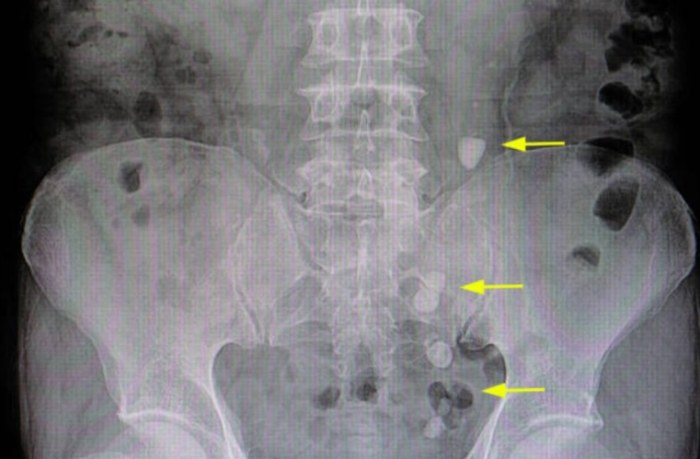

在所有「膀胱結石檢查」工具中,「腹部X光」是最快速的第一線工具。多數含鈣結石會在X光片上清晰顯現白色影子,讓我們快速掌握結石位置、大小和數量。然而,尿酸結石在X光下是隱形的,這時就需要進階檢查。